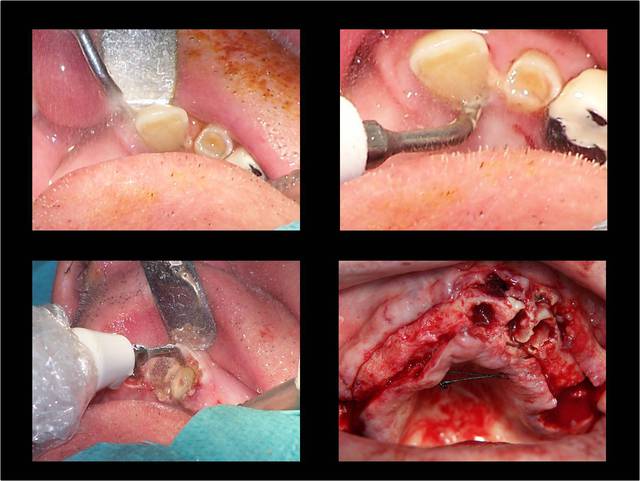

La vidéo présente à partir des plans de traitements, des chirurgies de beotien , des dispositifs médicaux sur mesure positdental et positguide la mise en charge immédiate post-extractionnelle d’un bridge provisoire à armature métal en prothèse fixe sur implants cône morse donc sans vis de maintien. Une question est émise « comment obtient-on ce résultat ? ». Une partie des réponses comme la prédictibilité, la reproductibilité peuvent y être déduite pour d’autre il faudra la bonté de beotien de faire partager les résultats clinique.il nous fait la générosité de poster la phase cicatriciel à 7 jours et des photos de la chirurgie sur un cas.

Je viens de revoir au cabinet un des 3 cas, car la céramique de la 25 était fracturée.

J'ai pris une photo (iphone) avec le bridge déposé avant de mettre temporairement le bridge coping de Posit. Pas la peine de commenter le bas je n'en suis pas responsable.